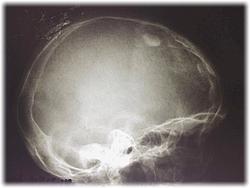

Внутренняя остеома, синдром Морганьи скорее всего.

На контур бы вывести. Действительно гиперостоз внутренней пластинки лобной кости и на остальном протяжении есть. Может и кальцинация менингиомы быть?

Может быть и остеома, может быть и образование. Без КТ не обойтись.

Олигодендроглиома, тоже может иметь кальцификаты?